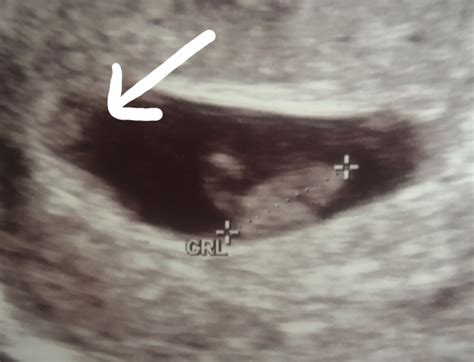

• Visualization of Embryos: At 7 weeks, the embryos are about the size of a blueberry. The ultrasound will show the gestational sacs, yolk sacs, and the fetal poles, which are the early forms of the embryos.

• Heartbeat Detection: In some cases, the fetal heartbeats may be visible, although it is not always detectable at this stage. The presence of a heartbeat is a positive sign of a viable pregnancy.

• Fetal Poles: Fetal poles are the early forms of the embryos and should be visible within the gestational sacs.

• Heartbeats: The detection of fetal heartbeats is a positive sign of a viable pregnancy, although it may not always be visible at 7 weeks.

📝 Note: The absence of a heartbeat at 7 weeks does not necessarily indicate a problem, as it may not be detectable at this early stage. Follow-up scans are usually recommended to monitor the development of the embryos.